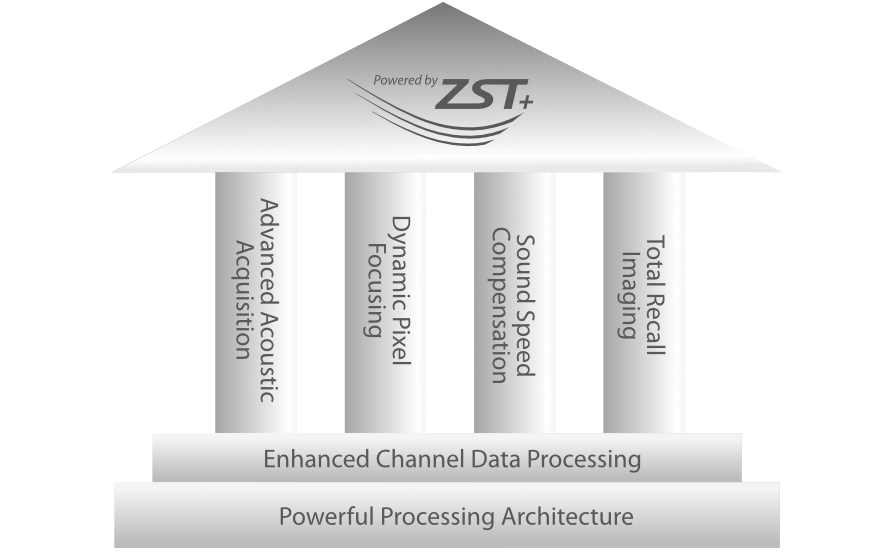

Full-stack Solution Powered by ZST?+

The ZST+ platform is an extraordinary innovation, representing an ultrasound evolution. Transforming ultrasound metrics from conventional beam-forming to channel data based processing. It overcomes the traditional trade-off limitation among spatial resolution, temporal resolution and tissue uniformity, delivering exceptional image quality for infinite imaging solutions with non-stop improvements.